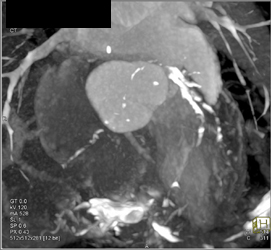

Diagnosis

Severe LAD